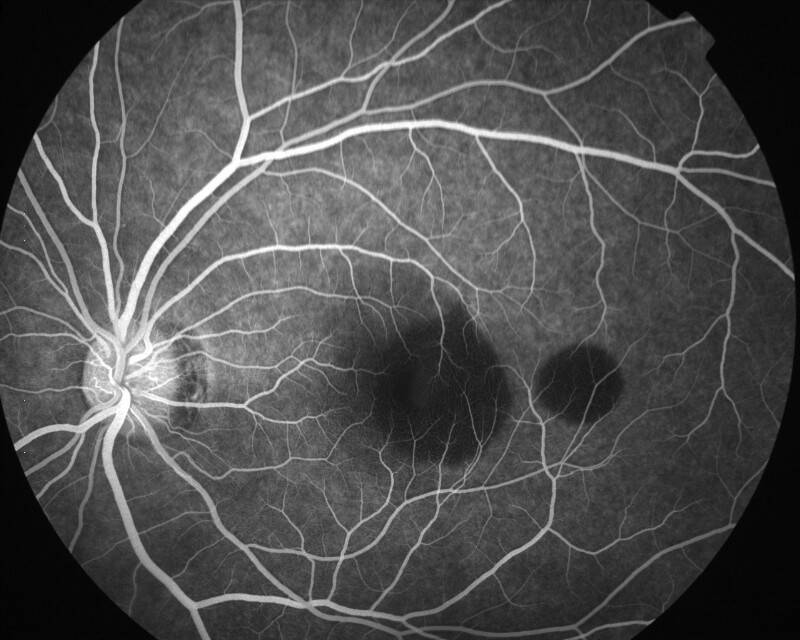

IMG0019.jpg